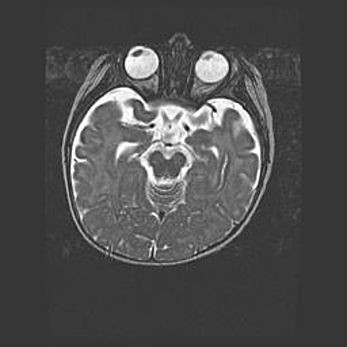

Наружная гидроцефалия с возможной атрофией височных областей.

Возраст: 28 дней

Вес: 3670 г

Пол: мужской

Окружность головы: 38 см

Срок гестации: 40 недель

Гидроцефалия головного мозга у новорожденных – это заболевание, которое характеризуется скоплением избыточного количества спинномозговой жидкости в желудочковой системе головного мозга в результате затруднения её перемещения от места выработки к месту поглощения в кровеносную систему или вследствие нарушения абсорбции. При открытой наружной форме гидроцефалии у новорожденных расширяются и переполняются субарахноидные пространства.

При нормотензивных  формах,  которые,  как  правило,  являются  следствием  перенесенных ишемических  повреждений  паренхимы  мозга,  возможно  сочетание микроцефалии  с нормотензивной гидроцефалией. В основе данных изменений лежит атрофия больших полушарий с преимущественной  локализацией  в  лобно-височных  областях.